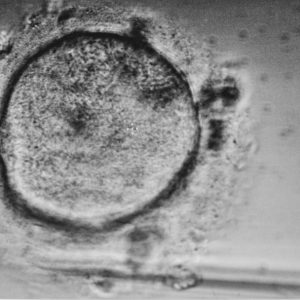

• Fertilização in vitro (ICSI);